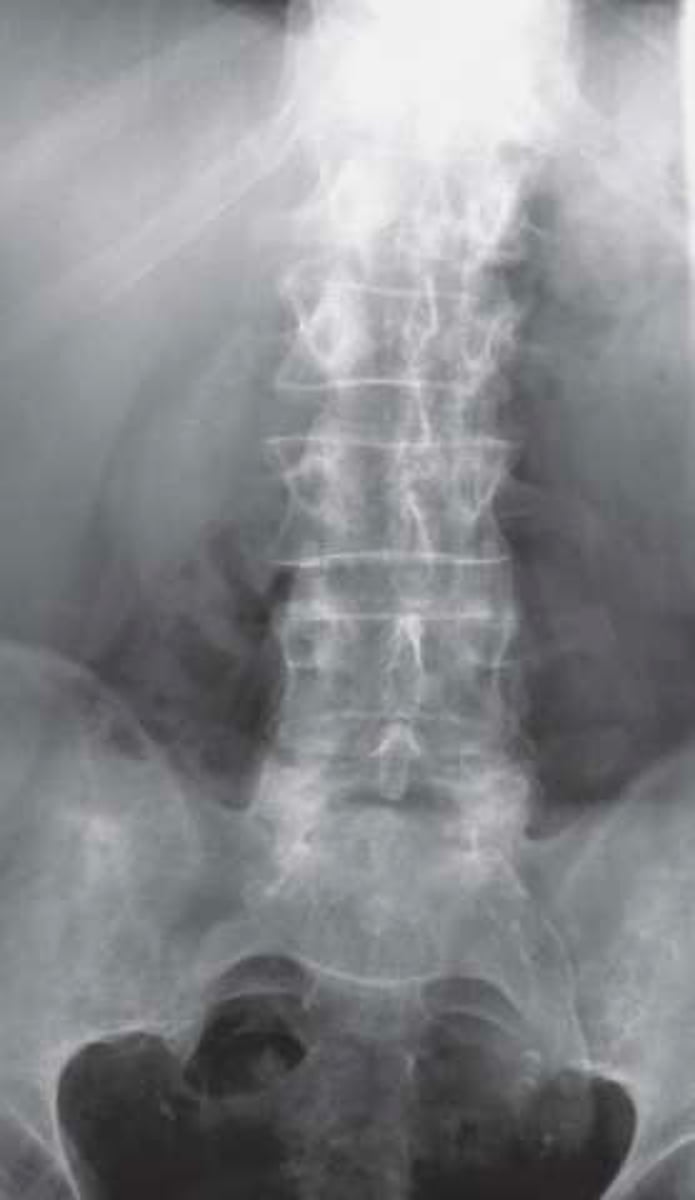

Vignette # 21

Sex: Male

Age: 22

Chief Complaint: Patient presents with insidious onset of low back pain and sacroiliac pain. He also reports having gastrointestinal issues.

Objective Findings: Forrestier's sign +, Chest expansion 1.25" Diagnostic imaging: X-ray

1. What are the radiographic signs expected in this condition? (Choose 3)

a. Shiny corner

b. Trolley track

c. Hiatal hernia

d. Unilateral SI sclerosis

e. Chondral sclerosis

f. Overhanging edge sign

g. Non-marginal syndesmophytes

h. Dagger sign

AS

Objective Findings: Forrestier’s sign +, Chest expansion 1.25” Diagnostic imaging: X-ray

2. What re the differential diagnoses? (Choose 3)

a. AS

b. Enteropathic arthropathy

c. Gouty arthritis

d. Psoriatic arthritis

e. Psoriatic arthritis

f. Osteitis condensans illi

g. Osteomyelitis

h. Bilateral sacroilitis

i. Reiter’s syndrome

3. What is seen in the progression of this condition? (Choose 3)

a. Anderson lesion

b. Carrot stick fracture

c. Hepatomegaly

d. Silver scales (psoriasis)

e. Pitted nails (psoriasis)

f. Erosion of joints (RA)

g. Overhanging edge sign (gout)

h. Anterior uveitis